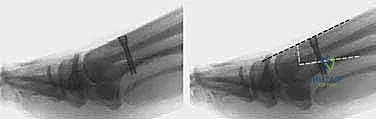

في العاصمة اليمنية صنعاء، يبرز اسم الأستاذ الدكتور محمد هطيف كعلامة فارقة والمرجع الطبي الأول في جراحة العظام والمفاصل وتصحيح تشوهات القدم والكاحل. يقدم الدكتور هطيف، متسلحاً بخبرة تتجاوز العقدين من الزمان، حلاً جراحياً ثورياً ومتقناً يُعرف باسم جراحة شفرون ثنائية المستوى لقطع العظم (Biplanar Distal Chevron Osteotomy). هذه التقنية الجراحية الدقيقة لا تكتفي بتصحيح الانحراف العادي، بل تعالج التشوهات المتوسطة والمتقدمة التي تتسم بزيادة معقدة في الزاوية المفصلية المشطية البعيدة (DMAA)، مما يعيد للقدم وظيفتها الميكانيكية الطبيعية وشكلها السليم.

* الزاوية المفصلية المشطية البعيدة (DMAA): في الحالات المتقدمة، يتشوه سطح المفصل نفسه ويميل بزاوية غير طبيعية. الجراحات التقليدية تفشل في علاج هذه الزاوية، وهنا تبرز أهمية تقنية شفرون ثنائية المستوى التي يطبقها الدكتور هطيف لتصحيح هذه الزاوية بدقة متناهية.

- DMAA (Distal Metatarsal Articular Angle): زاوية سطح المفصل، وهي الزاوية الأهم التي تحدد الحاجة لتقنية "ش